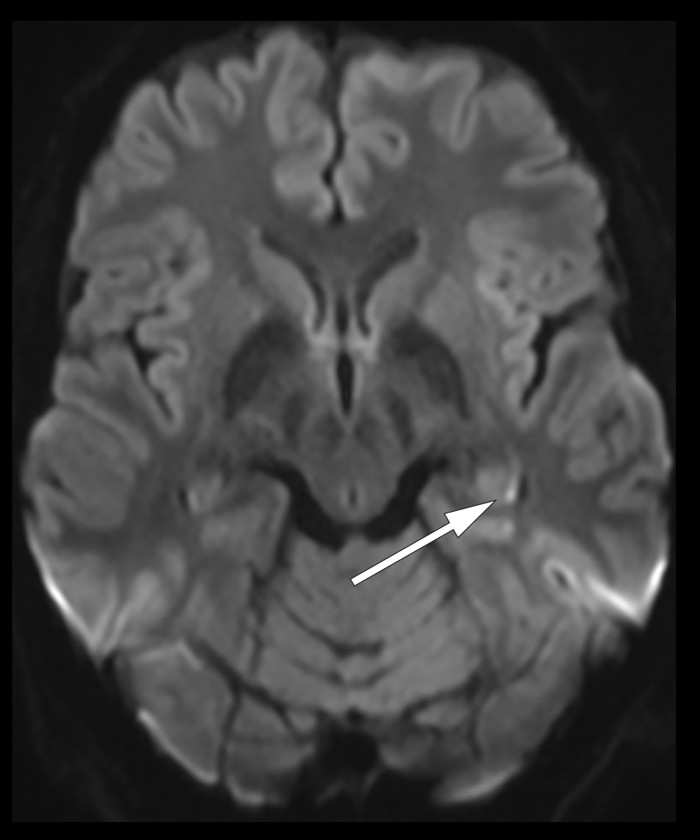

Ved klinisk undersøkelse i akuttmottaket ble det, utover anterograd amnesi, ikke funnet aktuelle nevrologiske utfall, og CT caput viste normale forhold. Ved videre undersøkelser to dager senere var det normalt EEG, uten tegn til epileptisk aktivitet. På diffusjonsvektet MR cerebrum så man et 2 mm stort område med diffusjonsforandringer i caudadelen av venstre hippocampus (pil). Slike subtile diffusjonsforandringer i hippocampus er typisk for transitorisk global amnesi (TGA) (1).